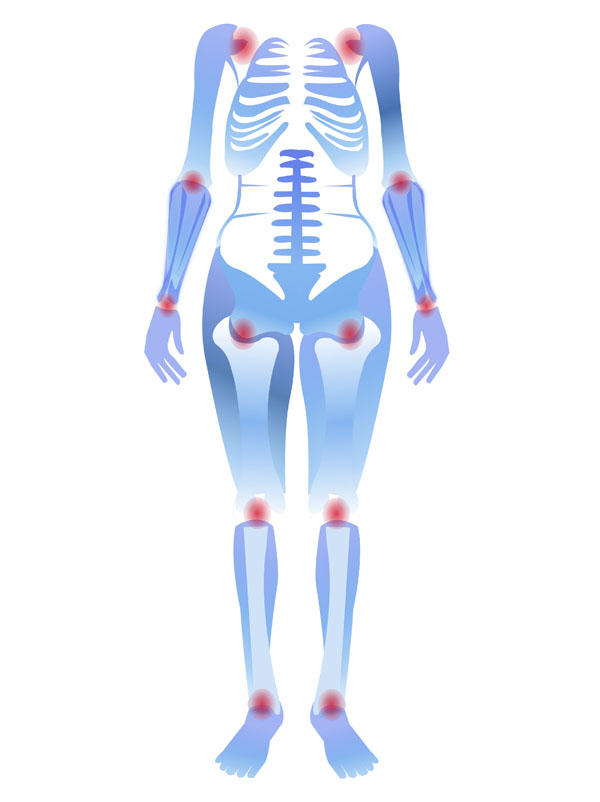

清晨下樓時膝蓋“咔咔”作響,爬兩層樓就酸脹發沉,久坐站起時關節像卡了鎖……這些場景是不是很熟悉?保護膝蓋的核心邏輯很簡單:減少損耗+增強支撐。做好以下四件事,讓膝蓋多“用”10年。

膝關節對寒冷刺激較為敏感,秋冬季節或長時間處于空調環境時,建議佩戴護膝做好保暖防護,減少寒冷誘發的關節不適。若關節出現持續性疼痛、腫脹,或伴隨關節變形、活動受限等情況,切勿強忍拖延,需及時就醫檢查干預。早期通過規范治療(如藥物調理、專業康復訓練等),能夠有效延緩軟骨磨損進程,保護關節功能。